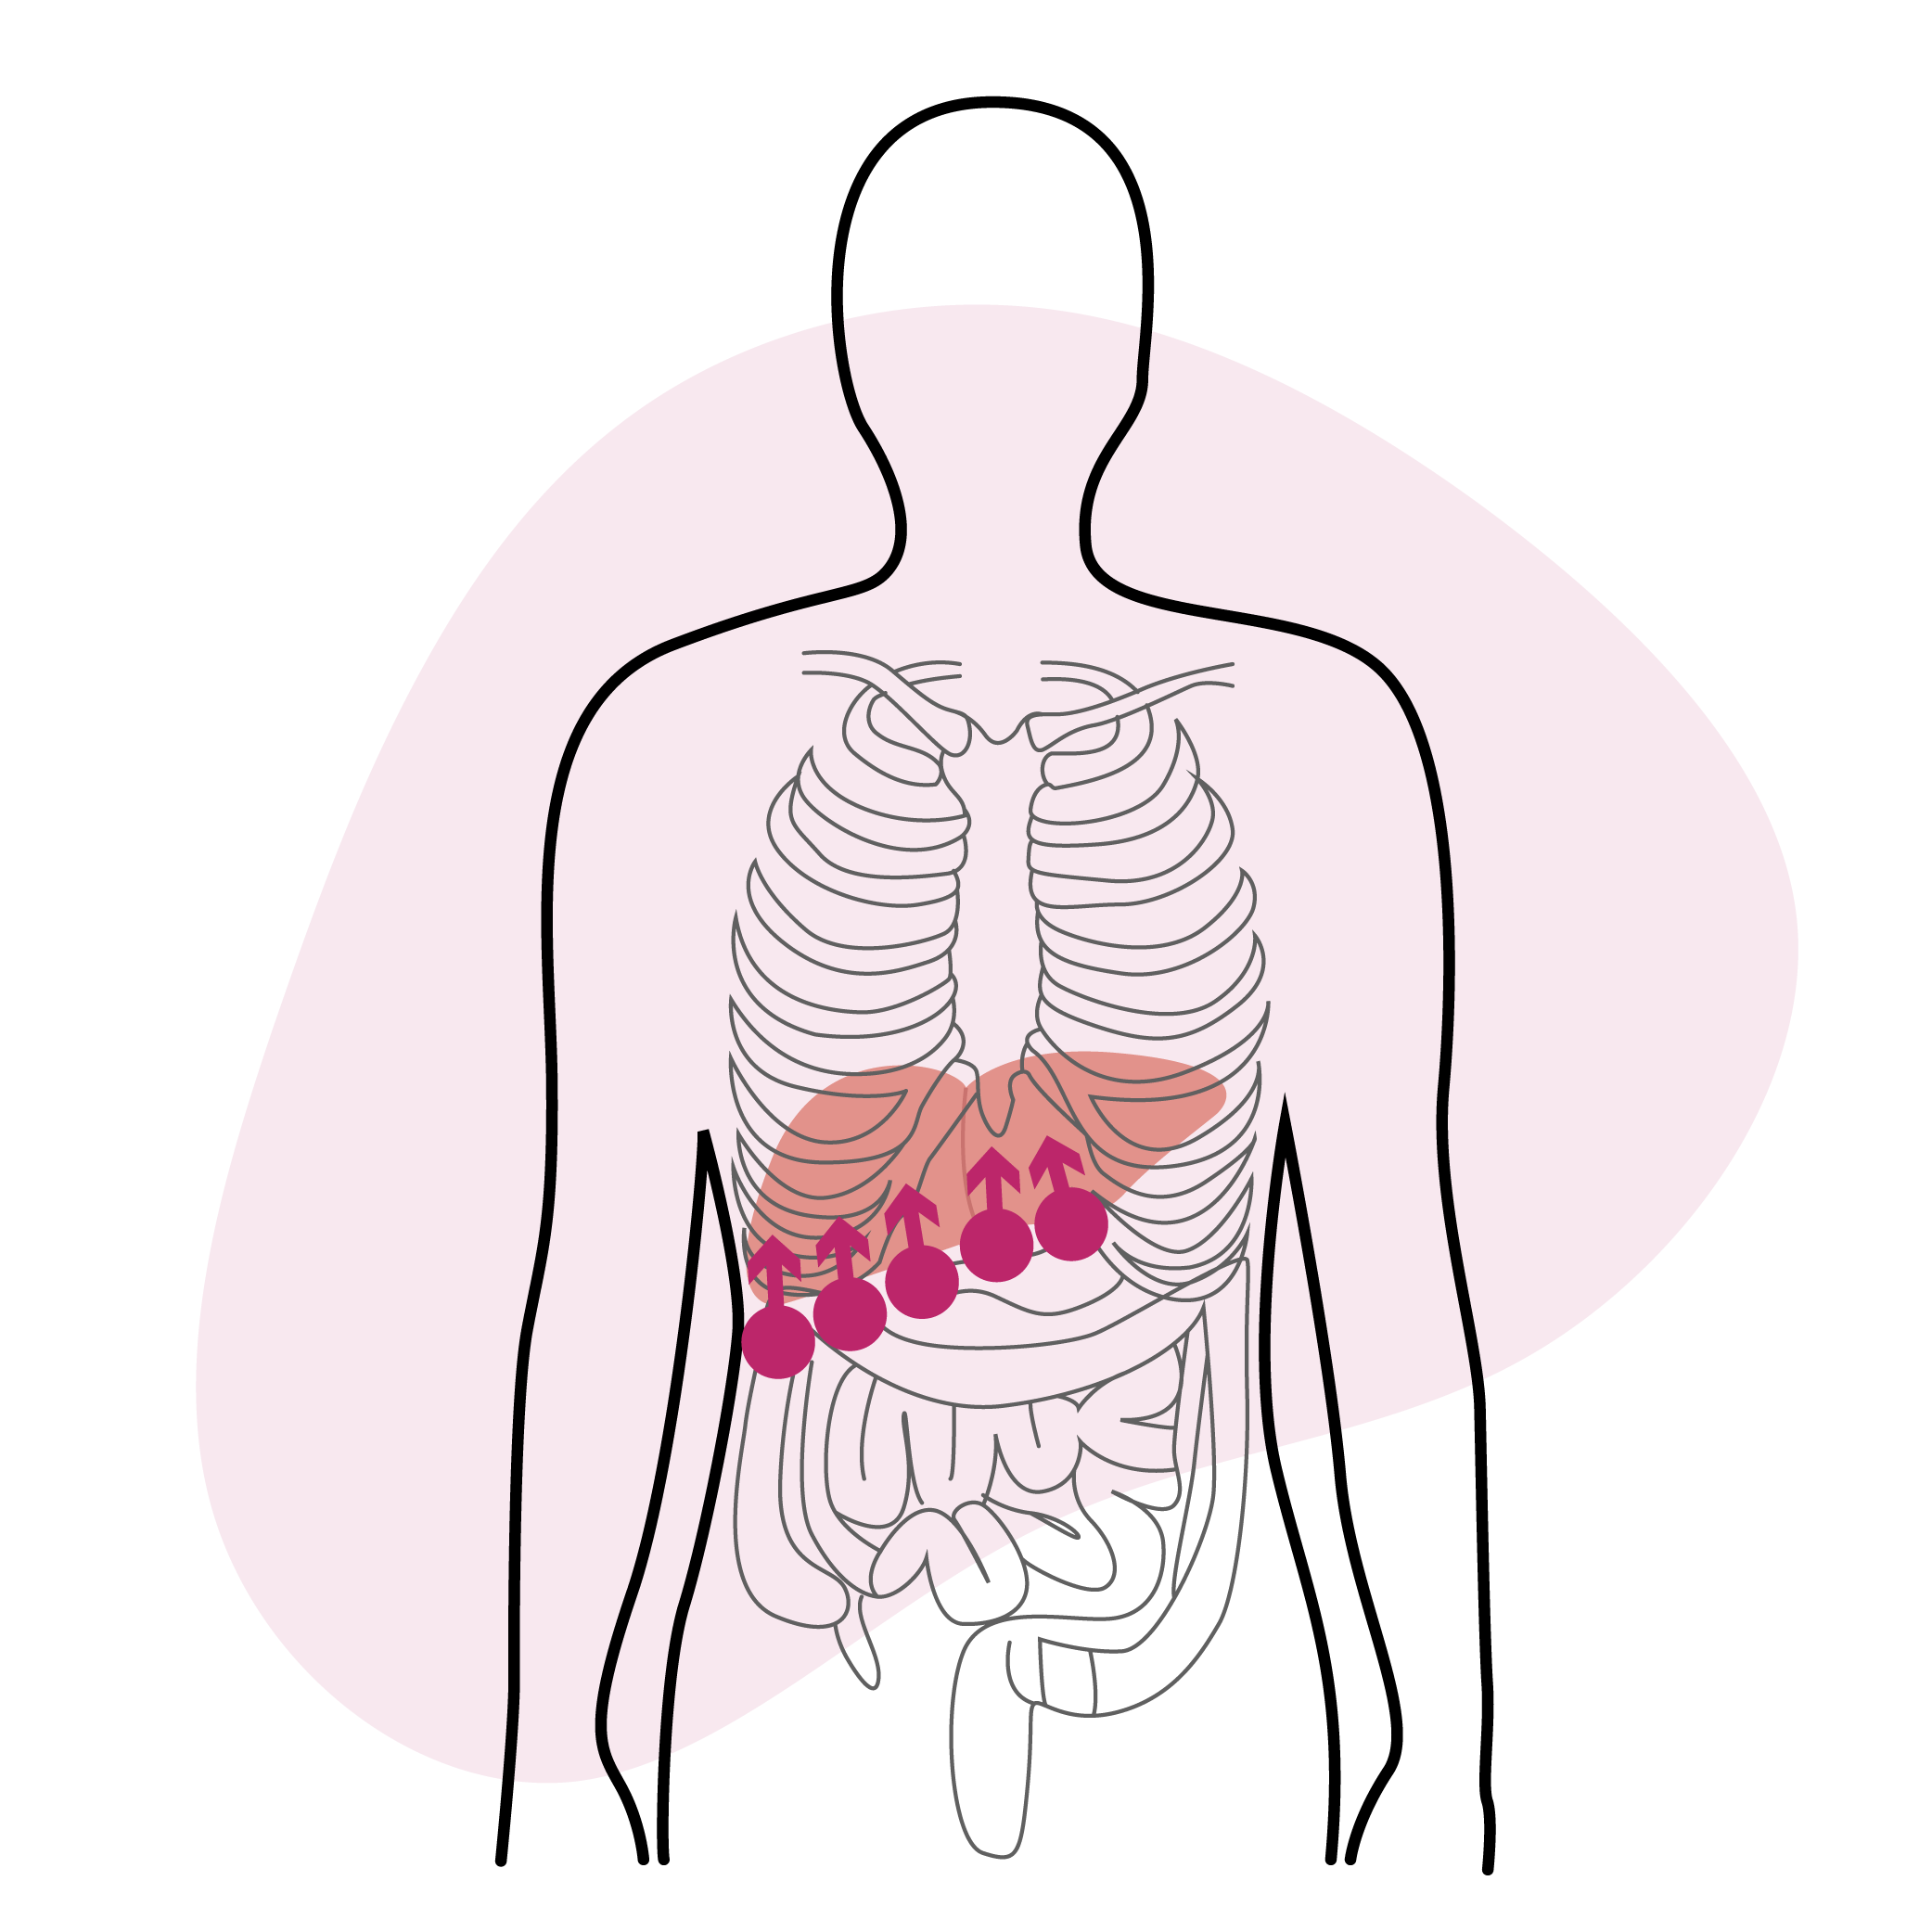

Libérer le foie

Libérer le foie